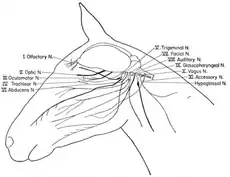

The cranial nerves in the horse

The cranial nerves in the horse Ventral view of a sheep's brain. The exits of the various cranial nerves are marked with red.